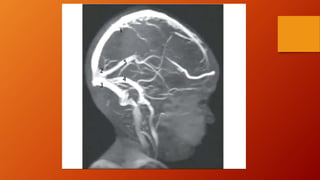

VASCULARIZACIÓN DE LA DURAMADRE.

• Las arterias de las dura madre aportan mas

sangre a la calvaria que a la duramadre.

• El mayor de estos vasos, la arteria meníngea

media, es una rama de la arteria maxilar.

• La rama frontal de la arteria meníngea media,

discurre superiormente al pterion y luego se

incurva posteriormente para ascender hacia el

vértice del cráneo.

• La rama parietal de la arteria meninge media.

• Las venas de la dura madre acompañan a las

arterias meníngeas a menudo por pares.

• Venas meníngeas medias acompañan a la arteria

meníngea media, abandonan la cavidad craneal

a raves del foramen espinoso o el foramen oval

y drenan en el plexo venoso pterigoideo.